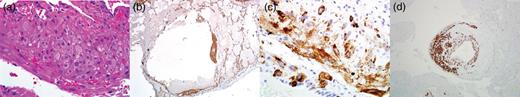

Upon admission, the patient's chest x-ray (CXR) was notable for bilateral interstitial infiltrates, and she was therefore started on empiric broad-spectrum antibiotics and oseltamivir. She was ventilated with lung-protective settings and paralyzed to alleviate ventilator dyssynchrony. Bronchoscopy revealed DAH and bronchioalveolar lavage cultures yielded Influenza A infection. She was started on high-dose methylprednisolone for her DAH, and inhaled nitric oxide (iNO) was added to optimize oxygenation. After a transient period of improvement, new infiltrates were appreciated on CXR, prompting computed tomography (CT) of her chest. This revealed multiple cysts throughout the lung parenchyma, suspicious for the diagnosis of LAM (Fig. 1).

CT chest (axial slices in lung window) demonstrating innumerable cysts scattered throughout all lung fields without basal/apical predilection or cardiophrenic sparing.